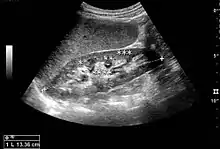

Figure 5. Simple renal cyst with posterior enhancement in an adult kidney. Measurement of kidney length on the US image is illustrated by '+' and a dashed line.[1]

Figure 6. Complex cyst with thickened walls and membranes in the lower pole of an adult kidney. Measurements of kidney length and the complex cyst on the US image are illustrated by '+' and dashed lines.[1]